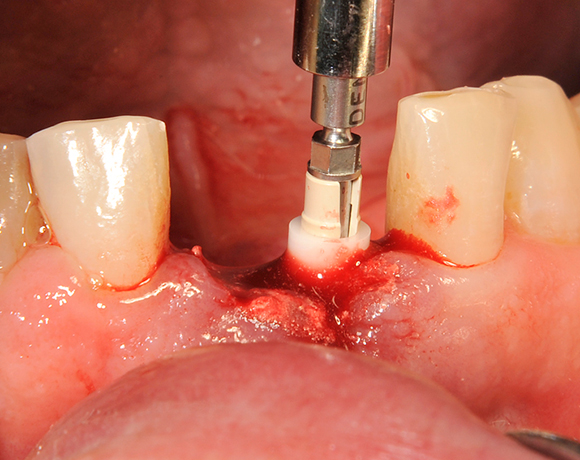

Die Keramikimplantate der Fa. Dentalpoint lassen sich auch zur Sofortimplantation verwenden. Das bedeutet, dass nach Extraktion nicht beherdeter Zähne direkt die Implantate gesetzt werden können.

Im vorliegenden Patientenfall wurden die beiden nicht erhaltungswürdigen, mittleren Unterkieferschneidezähne durch zwei Vollkeramikimlpantate ersetzt.